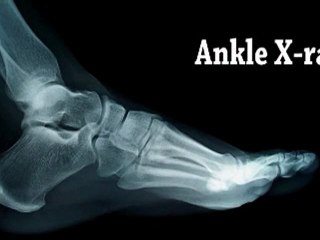

When you are a runner, the last thing you want is an injury. Dr Gibson discusses ways to limit injury and improve your running.